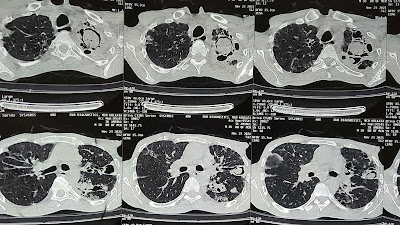

The Difference Between 'MONOD SIGN' vs 'AIR CRESCENT SIGN' and the 'BEST DRUMSTICK CLUBBING' - all in one patient.

MONOD sign is seen in ASPERGILLOMA or any Fungal Ball in a pre existing cavity ....Here the 1st 2 images are showing Monod sign, in contrary Air CRESCENT sign seen in Invasive Aspergillosis in RECOVERY phase as invasion reduce air seen between fungus and cavity wall.

Are are from a same patient...as his history was past history of un treated TB which leads to healing by fibrosis and broncheactasis leads the clubbing and also colonization with aspergilloma. He was complaint of occasional harmoptysis. We planned him for FOB (Bronchoscopy) guided intra- cavity Amphotericin- B for consecutive 5 days.